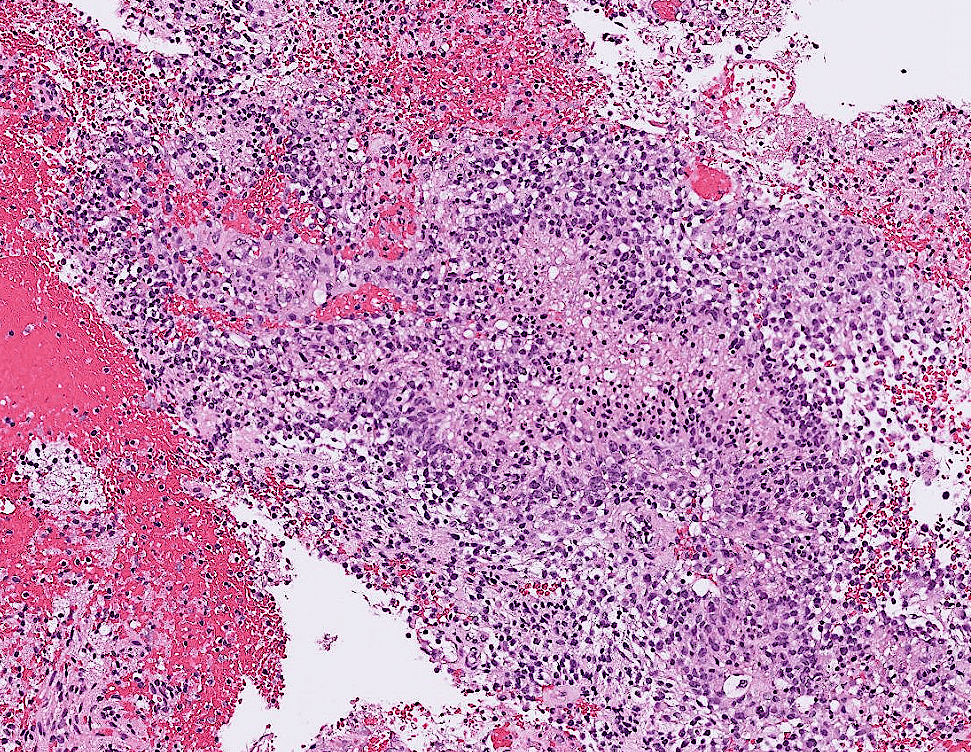

腺癌(Adenocarcinoma)

pictures from Pathology Outlines

Signet Ring Cell Pattern